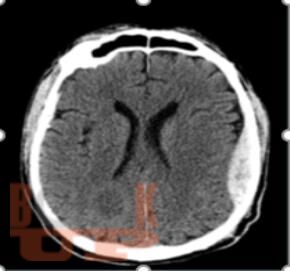

Интенсивная терапия внутричерепной гипертензии

Учебное пособие предназначено для ординаторов и слушателей курсов повышения квалификации по специальностям «Анестезиология и реаниматология», «Неврология», «Нейрохирургия». В настоящем учебном пособии освещены ключевые подходы к диагностике и оказанию помощи при внутричерепной гипертензии. Имеются тестовые задания и ситуационные задачи для самоконтроля знаний.